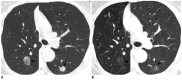

Tumor response may be assessed readily by the use of Response Evaluation Criteria in Solid Tumor version 1.1. However, the criteria mainly depend on tumor size changes. These criteria do not reflect other morphologic (tumor necrosis, hemorrhage, and cavitation), functional, or metabolic changes that may occur with targeted chemotherapy or even with conventional chemotherapy. The state-of-the-art multidetector CT is still playing an important role, by showing high-quality, high-resolution images that are appropriate enough to measure tumor size and its changes. Additional imaging biomarker devices such as dual energy CT, positron emission tomography, MRI including diffusion-weighted MRI shall be more frequently used for tumor response evaluation, because they provide detailed anatomic, and functional or metabolic change information during tumor treatment, particularly during targeted chemotherapy. This review elucidates morphologic and functional or metabolic approaches, and new concepts in the evaluation of tumor response in the era of personalized medicine (targeted chemotherapy).